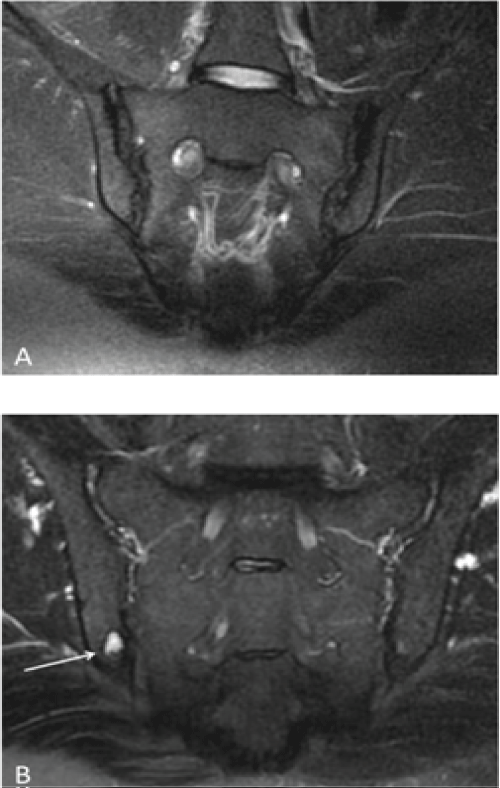

A total of 101 patients were assessed. All patients had LS-related pathology (the most common pathologies were disc herniation and bulging). Seventy-five (73%) patients only presented with a LS abnormality (29 females and 45 males; mean age, 46 ± 14 years; range, 16-79), whereas twenty-six patients (26%) were diagnosed with a combination of LS and SIJ pathology (17 females and 9 males; mean age, 48.1 ± 14 years; range, 28-79), as shown in Table 2. Chronic changes were most frequently encountered in SIJ patients (16% of the SIJ patients). As shown in Figure 2A, some cases showed significant bilateral chronic changes (grade 3 and 4 on the right and left, respectively) in the form of irregular articular margins and dense sclerosis involving > 90% of the left iliac portion and approximately 40% of the superior right iliac segment of the SIJ.

Figure 2: A) A 40-year-old female presented with LBP radiating to the left lower limb. The figure shows a radial T2-W FS image of the SIJ (the loss of signal on the left [large arrow] is greater than the loss on the right side [small arrow]) shows chronic changes in the form of irregular articular margins and dense sclerosis, which were more extensive on the left side (grade 3) than on the right (grade 2); B) A 54-year-old male presented with LBP radiating to both lower limbs; radial MRI of the SIJs revealed a focal area of sclerosis involving the inferior articular margin of the right iliac bone with well-defined erosion and active subchondral edema (arrow).  View Figure 2

Radial MRI scans were evaluated according to signal changes within the SIJs. Normally, the SIJ space has a symmetric and homogeneous signal intensity in all sequences. An atypical signal intensity pattern of the joint space includes an intermediate signal on T1-W images and a high signal on T2-W and PD images [19]. Examples of focal, high T2-W signal changes are shown in Figure 2B and were confined to the inferior portion of the articular margin of the right iliac bone, indicating a focal area of subchondral edema and erosion. The high T2-W signal suggested active disease. Generally, most incidences of SIJ abnormalities were evident on the radial MRI scans and were depicted as abnormal signal changes within the joint and surrounding bone.